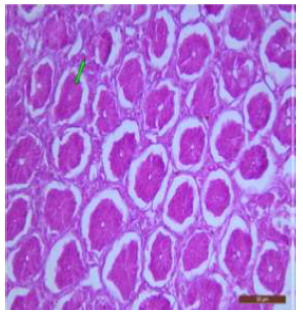

The duodenum of control rat showed histological features such as presence of different layers such as mucosa, submucosa, muscularis and serosa. The lining of epithelium of microvilli was composed of many cell types such as goblet cells, Paneth cells and absorptive columnar epithelial cells (Figure 1). Brünner’s glands were seen in the submucosal region of the duodenum which secrete alkaline fluid containing mucin (Figure 2). The rats treated with 600mg/kg b.w./day for 40 days revealed thickened and scattered villi (Figure 3). Hypertrophy of goblet cells and damaged crypts were also observed. (Figure 4). The necrotic Brünner’s gland showed inflammation and dilation of spaces (Figure 5).

Figure 1: T.S. of duodenum of control rat showing crypts (↑), closely packed microvilli (↑), well developed submucosa and muscularis externa. H&E × 100.